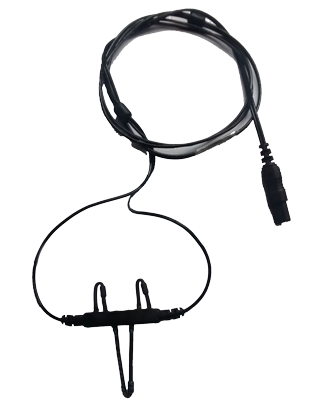

Os Eletrodos Concha de Prata são a escolha profissional para exames de EEG e PSG, combinando alta qualidade técnica e segurança. Fabricados com conector Touch Proof (pino de segurança), concha banhada a ouro e fios de Kevlar ultra-resistentes, garantem durabilidade excepcional e precisão na captação de sinais elétricos cerebrais.

– Fios de Kevlar: resistentes a torções, trações e desgaste, ideais para uso intensivo.

– Conector Touch Proof: Elimina riscos de interferência e aumenta a segurança do paciente.

– Kevlar: Material 5x mais resistente que aço, ideal para ambientes de alta demanda.